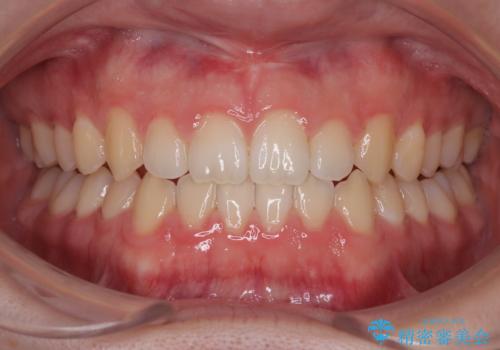

すきっ歯は放置NG?インビザラインで目立たず改善

- 「前歯のすきっ歯が気になる」「食べ物が歯の間に詰まりやすい」とのお悩みで来院された20代男性の患者様です。

歯と歯の間に隙間がある**空隙歯列(すきっ歯)**は、見た目の問題だけでなく、食片圧入による歯肉の腫れや、隣接面う蝕のリスク増加につながることがあります。

患者様は「できるだけ目立たない矯正治療」を希望されていたため、インビザラインを用いた治療計画を立案しました。